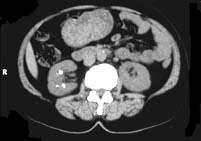

问题 女,26岁,右腰部不适2年,影像检查如图所示,应诊断为 ( )

选项 A、右侧慢性肾小管酸中毒 B、维生素D中毒所致的右肾改变 C、右肾结核瘤 D、甲旁亢所致的右肾改变 E、右侧髓质海绵肾

答案 E